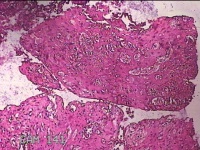

子宫左侧壁残留妊娠物

性别

女

年龄

40岁

临床诊断

稽留流产 药流失败 宫腔粘连

一般病史

停经5月余,要求终止妊娠。

标本名称

大体所见

灰白暗红色不规则碎组织1.5x1.3x0.3cm一堆,内有少许绒毛样组织。

见胎盘绒毛。

凝血中见退 变蜕膜和机化绒毛。